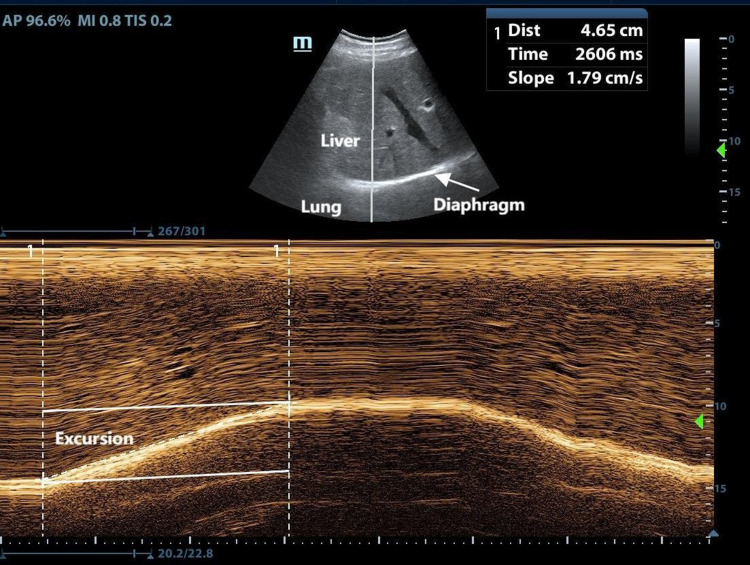

Methods: This study consecutively enrolled 75 COPD patients and 75 healthy subjects. Measurements of diaphragm contraction, motion-related parameters and tissue Doppler imaging (TDI) parameters were conducted and recorded. Clinically relevant data were collected. Baseline demographics, spirometry results, and ultrasound data were compared between COPD patients and healthy subjects. Receiver Operating Characteristic (ROC) curve was constructed to evaluate the diagnostic value of diaphragmatic ultrasound parameters for COPD patients.

Results: Diaphragm at the end of tidal inspiration (DT_insp), diaphragm thickening fraction (DTF), diaphragmatic excursion during deep breathing (DE_DB) were significantly lower in COPD patients than in healthy subjects, conversely diaphragmatic excursion during quiet breathing (DE_QB), diaphragmatic contraction velocity during quiet breathing (DCV_QB), peak contraction velocity(PCV), peak relaxation velocity (PRV), velocity-time integral (VTI) were higher in COPD patients than in healthy subjects. DT_insp, DTF, DE_DB values decreased as COPD severity increased, conversely, DE_QB, DCV_QB, PCV, PRV and VTI exhibited an upward trend with COPD severity. DTF was positively correlated with FEV1 predicted (r=0.713, P=0.000), DE_QB (r=-0.740 and -0.889), PCV (r=-0.609 and -0.778), PRV (r=-0.686 and -0.857) were negatively correlated with FEV1/FVC and FEV1 predicted (P=0.000). Meanwhile, DE_QB, DCV_QB, PCV and PRV exhibited superior performance in predicting COPD, with AUC values of 0.906, 0.833, 0.859 and 0.833, respectively. DE_QB exhibited 81.33% sensitivity, while DTF, DE_QB, DE_DB, PCV and PRV showed high specificity (98.67%, 90.67%, 96.00%, 97.33% and 100%, respectively).